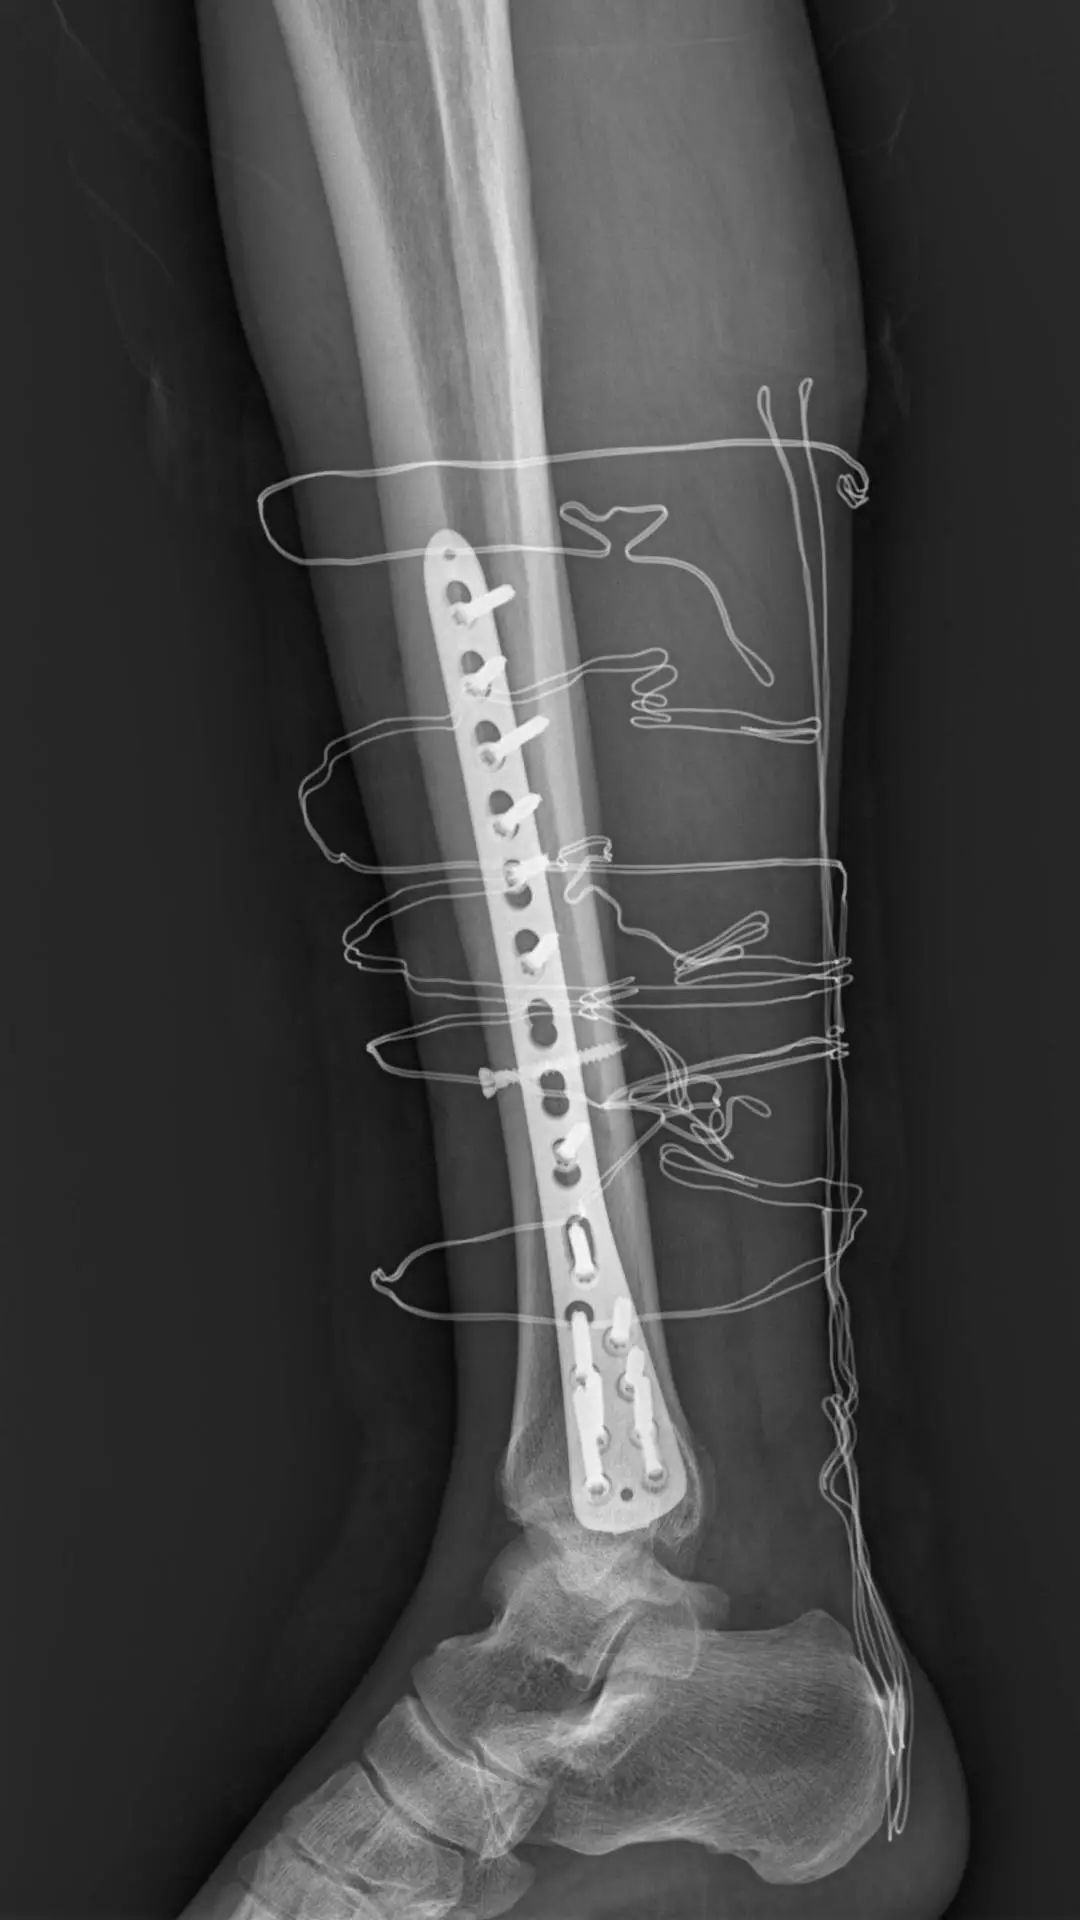

检查显示:胫骨下段粉碎骨折,右腓骨近端粉碎骨折

随即收治入院,由于胫腓骨都有骨折,引起腓总神经损伤,如果压迫时间久会造成神经的不可逆修复,黄淮医生评估病情后决定开展急诊手术。完善各项术前相关检查,各项指标均正常,经过详细的评估,骨科团队商讨后决定微创治疗,减少对患者身体的创伤,为顾老伯制定了周密的手术方案。

在麻醉科、手术室的密切配合下,仅1小时10分钟,手术顺利结束。

如果按照传统的手术方法做多段的胫骨骨折,切口是从最高点的骨折端到最低点的骨折端,感染的风险增加,对周围软组织的损伤,会遗留明显的疤痕。微创手术的优点